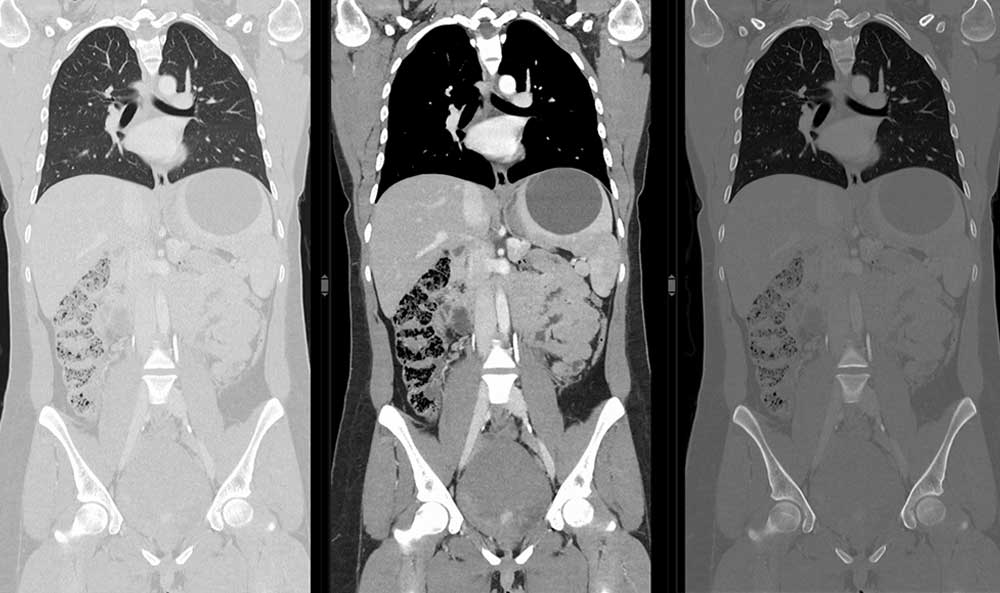

Drei CT-Bilder eines Brustkorbs mit Lungen, Herz und Bauchorganen in unterschiedlichen Durchleuchtungsstufen.

Die Computertomographie schafft eine volumetrische Darstellung unterschiedlicher Körperregionen. Mit einem rotierenden Röntgenstrahlenbündel strahlen wir den Körper durch. Die geschwächten Projektionen lesen wir durch einen Detektor aus und speichern sie in einer Matrix (Rohdatensatz). Ein Computer berechnet anschließend zweidimensionale oder dreidimensionale Bilddatensätze durch den menschlichen Körper. Die Computertomographie ist eines der wichtigsten radiologischen Verfahren. Sie diagnostiziert unterschiedliche Erkrankungen – u.a. Lungengerüsterkrankungen, Tumore, Knochenbrüche, Blutungen und Entzündungen.